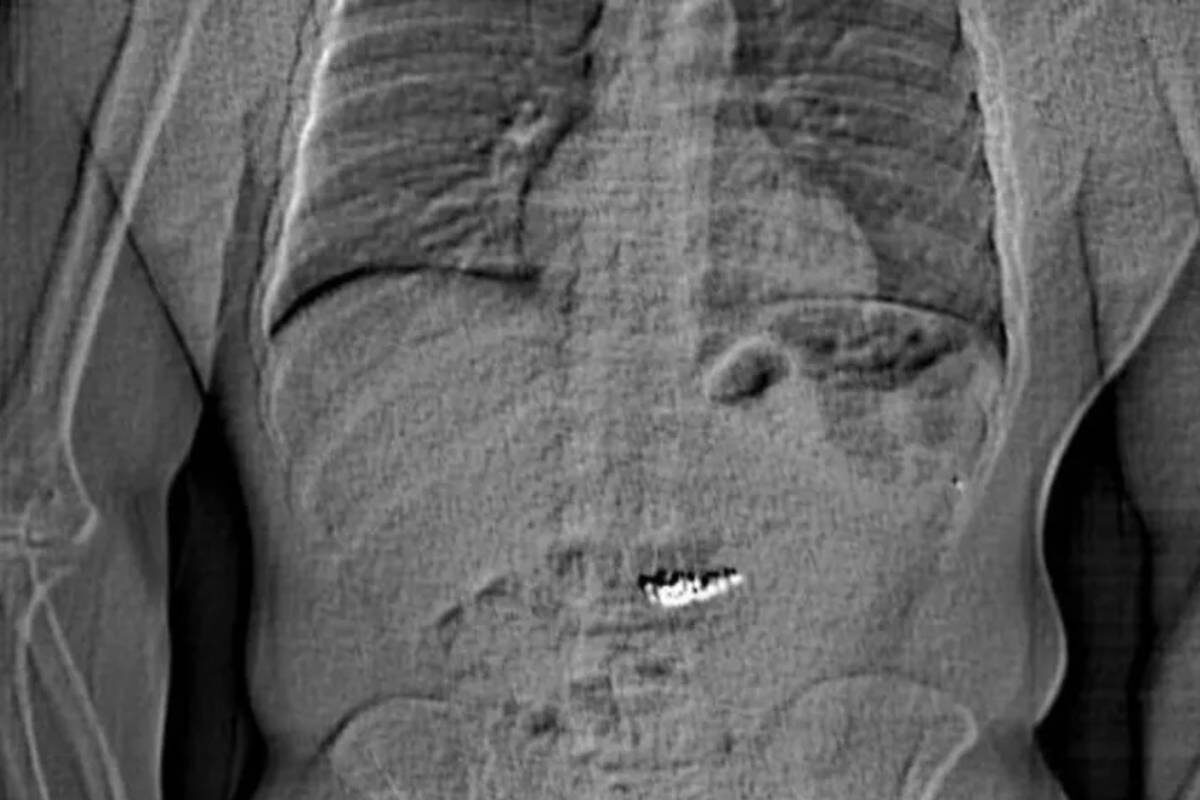

Radiografía del estómago del detenido

Como la policía había visto a Gilder tragarse algo justo antes de ser detenido…. Se les ocurrió realizarle una radiografía del torso. En la misma se puede observar claramente una masa blanca que brillaba intensamente contra el fondo gris de su tracto digestivo. "Se sospecha que estos objetos extraños son los pendientes de Tiffany & Co que se llevaron en el robo, pero será necesario recogerlos… después de que los expulse", decía el informe de arresto del departamento. Por el momento, la policía de Orlando no ha confirmado si ya se habían recuperado los pendientes o en qué estado se encontraban.